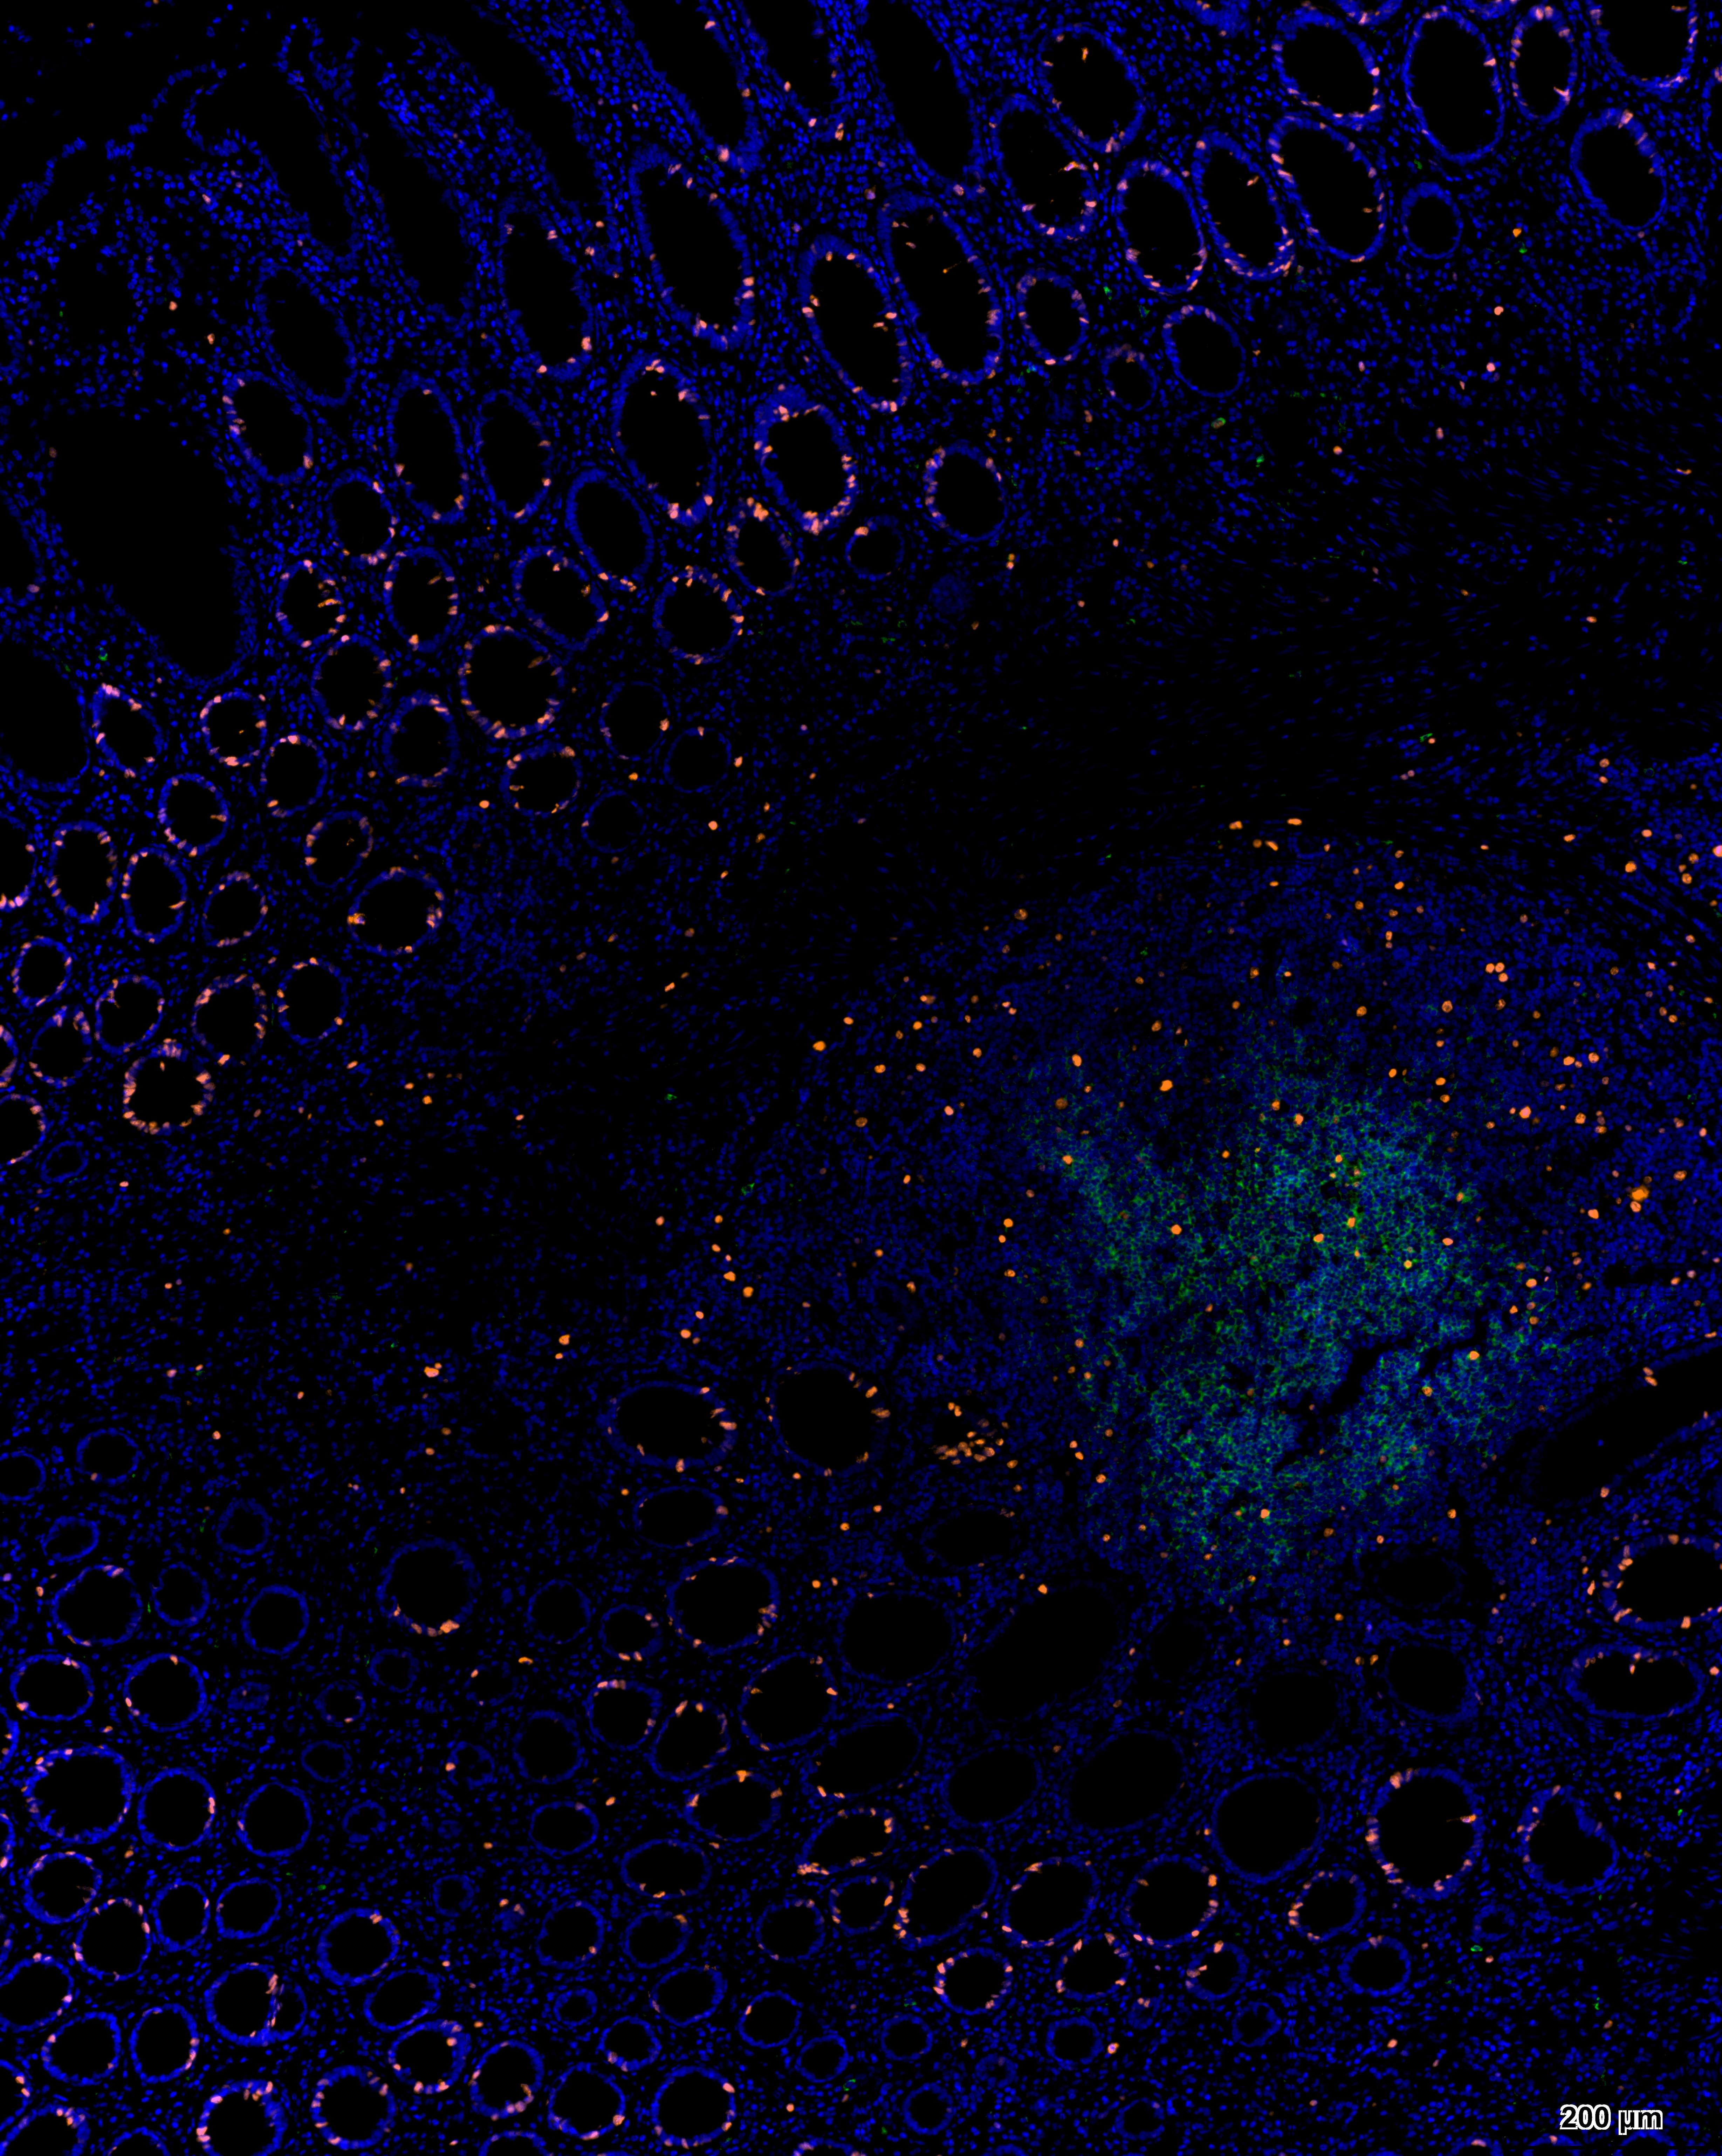

Immunohistochemical analysis of paraffin embedded intestinal cancer tissue slide using IHCT001 (Three Color mIHC Fluorescence Kit).